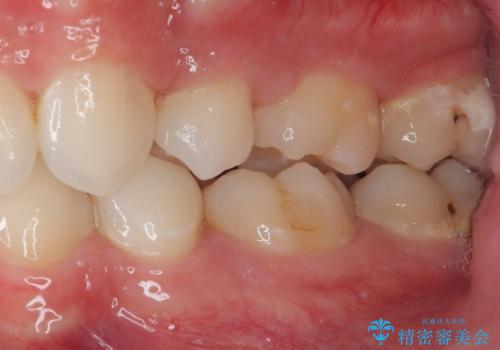

- 今回ご紹介するのは、

「全体的なデコボコ(叢生)」「上下の正中のずれ」 を主訴として来院された20代男性の患者様の症例です。

叢生が強く、歯が並ぶスペースが不足していたため、

上下左右の第一小臼歯を抜歯して、矯正治療のための適切なスペースを確保する計画としました。

叢生によるデコボコがあると、歯ブラシが届かない部分が多くなり、

虫歯リスクの上昇

歯周病の悪化

につながりやすい状態になります。